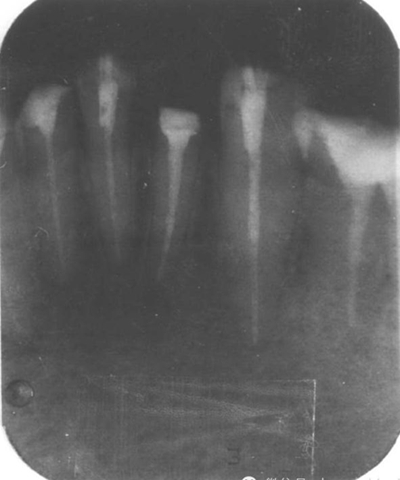

4.用匹配的鉆石擴(kuò)大至最初的直徑,用X光檢查。

5.重新安裝新的樁核等材料。通過X光片檢查以上步驟。

手術(shù)后